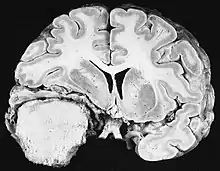

Les tumeurs des cellules gliales les plus courantes et les plus malignes sont les glioblastomes. Ils consistent en une masse hétérogène de cellules d'astrocytome peu différenciées principalement chez l'adulte. Ils surviennent généralement dans les hémisphères cérébraux, plus rarement dans le tronc cérébral ou la moelle épinière. Sauf dans de très rares cas, comme toutes les tumeurs cérébrales, elles ne s'étendent pas au-delà des structures du système nerveux central.

Le glioblastome peut provenir d'une forme diffuse (II. grade) ou un astrocytome anaplasique (III. grade) développer. Dans ce dernier cas, il est dit secondaire. Cependant, lorsqu'elle survient sans antécédent ni signe de malignité antérieure, on parle de maladie primaire. Les glioblastomes sont traités par chirurgie, radiothérapie et chimiothérapie. Ils sont difficiles à guérir et rares sont les cas qui survivent au-delà de trois ans.